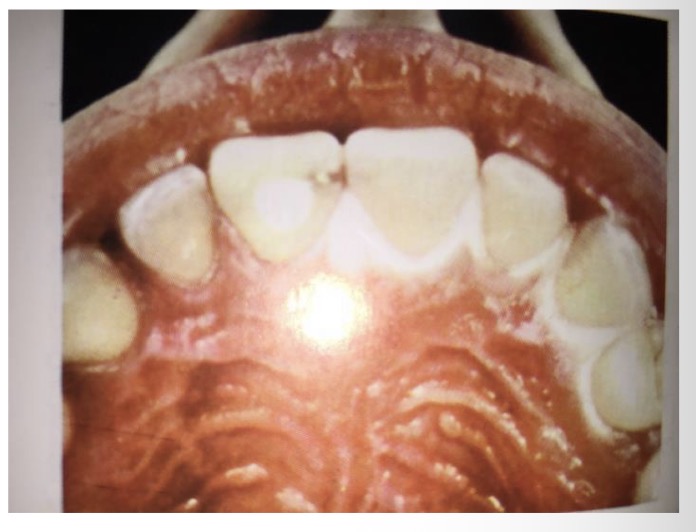

CHẨN ĐOÁN ?

SÂU RĂNG SAU XẠ TRỊ( sâu nhiều răng và lang quanh cổ răng)